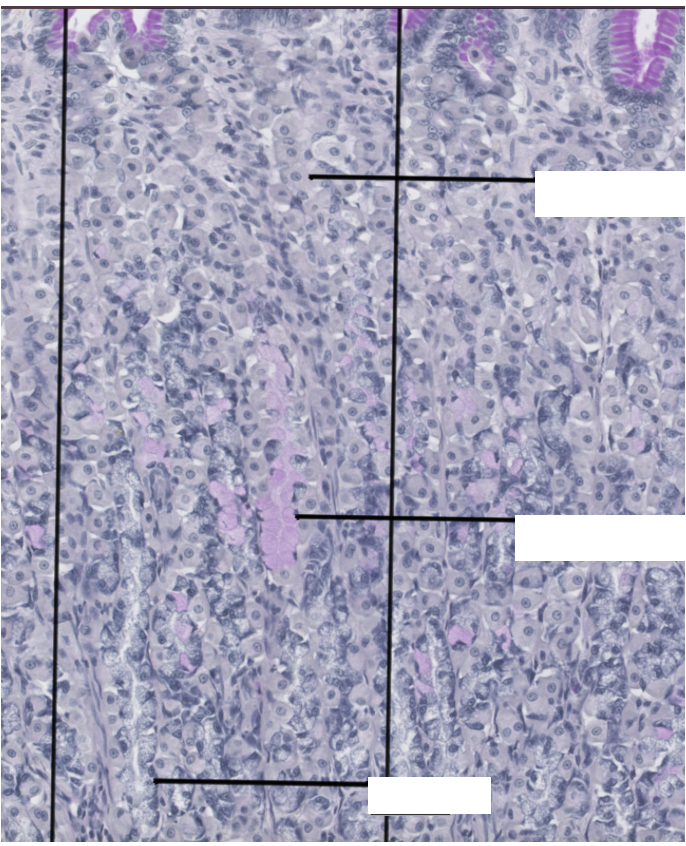

Describe what you can see in the histological images- where in the lesion does this tissue section come from?

Loss of glandular tissue on LHS

Inflammation causes hyperplastic inflammation to local tissues

What can you see in this image?

Looks like a ruptured artery-which may explain vomit

Completely ulcerated mucosa

Loss of muscularis layer

Scar tissue- pale and pinkish

Bottom part: muscle with canals of lymphocytes and slits in the faded part are blood vessels

Blood vessels and lymphocytes